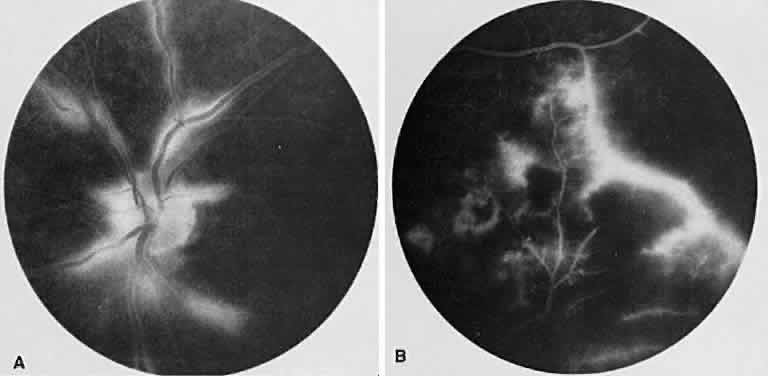

The FA reflects the various clinical entities. Retinal venular walls stain, particularly where there are perivenular exudates.25–27 More extensive venous involvement can produce a picture of dilated veins and perivenous leakage.27 Peripheral neovascularization occurs near areas of retinal capillary nonperfusion.25,28 Optic disc granulomas and optic disc neovascularization both leak extensively (Fig. 8A); sarcoid retinal lesions also stain (see Fig. 7B).27 In disc edema, the disc is hyperfluorescent and leaks fluorescein (see Fig. 8B).25

Fig. 8. Sarcoidosis. A. Fluorescein angiography shows two separate areas of neovascularization of the peripheral retina. B. Extreme leakage of dye from the right disc with cystoid macular edema of the right macular region in a patient with chronic sarcoidosis.